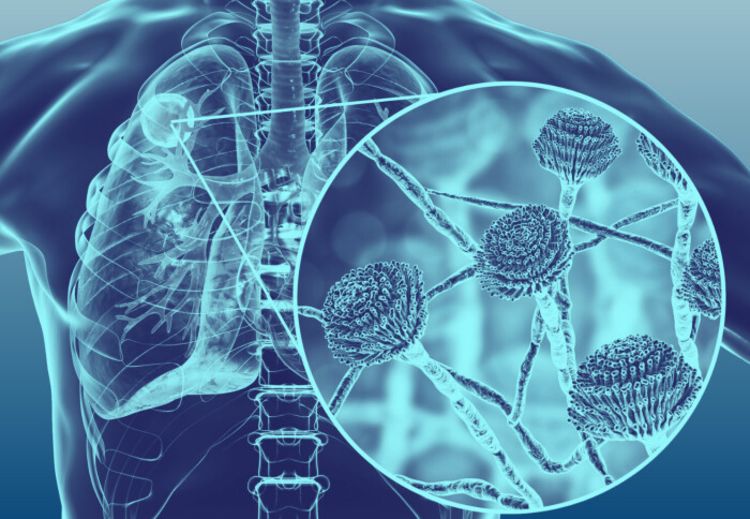

4 key things to know about lung infections caused by fungi discount, Frontiers Pathogenic Fungal Infection in the Lung discount, Fungal Pneumonia Overview Risk Factors Epidemiology of Fungal discount, Pulmonary aspergilloma Information Mount Sinai New York discount, 3 common types of lung fungus Vinmec discount, Fungal Lung Disease Makes World s Deadliest Bacteria Even Worse discount, Fungal infections of the lung in children Pediatric Radiology discount, World s first clinical guidelines for chronic fungal lung infections discount, Pulmonary fungal infection Imaging findings in immunocompetent discount, Frontiers Recent Advances in Fungal Infections From Lung discount, Fungal Pneumonia Overview Risk Factors Epidemiology of Fungal discount, Pulmonary fungal infection Imaging findings in immunocompetent discount, Is it TB or a fungal lung infection New life saving guidelines discount, Fungal pneumonia causes symptoms diagnosis treatment discount, COVID 19 associated pulmonary aspergillosis caused by aspergillus discount, Fungi are present in your lungs Faculty of Medicine UiB discount, Aspergillus Pneumonia Appears to Be Most Common Fungal Infection discount, CT image of lung with pulmonary Candida infection. There are many discount, A Schizophyllum commune fungus ball in a lung cancer cavity a discount, Fatal Fungal Lung infection affects TB recovered patients due to discount, Respiratory Mycoses Microbiology discount, Pulmonary fungal infection Imaging findings in immunocompetent discount, What is Aspergillosis Fungal Infections Symptoms Video discount, Blastomycosis Wikipedia discount, How nanoparticle drug inhalation helps fungal lung infections discount, Aspergillosis Types of Fungal Diseases Fungal Diseases CDC discount, Fungal pneumonia Wikipedia discount, Frontiers Candida Colonization in the Respiratory Tract What Is discount, How to fight fungal infection the path of yeast resistance discount, Pulmonary aspergilloma Information Mount Sinai New York discount, Fungal Infection Not Just Toenails Blueberry Therapeutics discount, Lung disease fungus grows here discount, Frontiers Case Report Invasive Fungal Infection and Daratumumab discount, A case report of fungal infection associated acute fibrinous and discount, Mice found able to ward off fungal lung infections by causing discount.

4 key things to know about lung infections caused by fungi discount, Frontiers Pathogenic Fungal Infection in the Lung discount, Fungal Pneumonia Overview Risk Factors Epidemiology of Fungal discount, Pulmonary aspergilloma Information Mount Sinai New York discount, 3 common types of lung fungus Vinmec discount, Fungal Lung Disease Makes World s Deadliest Bacteria Even Worse discount, Fungal infections of the lung in children Pediatric Radiology discount, World s first clinical guidelines for chronic fungal lung infections discount, Pulmonary fungal infection Imaging findings in immunocompetent discount, Frontiers Recent Advances in Fungal Infections From Lung discount, Fungal Pneumonia Overview Risk Factors Epidemiology of Fungal discount, Pulmonary fungal infection Imaging findings in immunocompetent discount, Is it TB or a fungal lung infection New life saving guidelines discount, Fungal pneumonia causes symptoms diagnosis treatment discount, COVID 19 associated pulmonary aspergillosis caused by aspergillus discount, Fungi are present in your lungs Faculty of Medicine UiB discount, Aspergillus Pneumonia Appears to Be Most Common Fungal Infection discount, CT image of lung with pulmonary Candida infection. There are many discount, A Schizophyllum commune fungus ball in a lung cancer cavity a discount, Fatal Fungal Lung infection affects TB recovered patients due to discount, Respiratory Mycoses Microbiology discount, Pulmonary fungal infection Imaging findings in immunocompetent discount, What is Aspergillosis Fungal Infections Symptoms Video discount, Blastomycosis Wikipedia discount, How nanoparticle drug inhalation helps fungal lung infections discount, Aspergillosis Types of Fungal Diseases Fungal Diseases CDC discount, Fungal pneumonia Wikipedia discount, Frontiers Candida Colonization in the Respiratory Tract What Is discount, How to fight fungal infection the path of yeast resistance discount, Pulmonary aspergilloma Information Mount Sinai New York discount, Fungal Infection Not Just Toenails Blueberry Therapeutics discount, Lung disease fungus grows here discount, Frontiers Case Report Invasive Fungal Infection and Daratumumab discount, A case report of fungal infection associated acute fibrinous and discount, Mice found able to ward off fungal lung infections by causing discount.